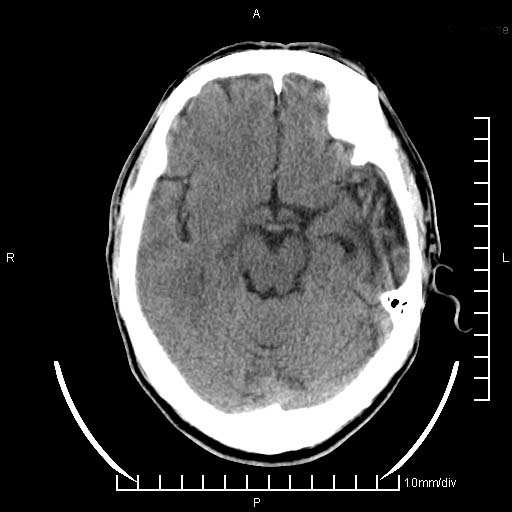

临床以双下肢浮肿,疼痛收治,无明显神经系统症状,既往无梗塞,出血病史。左颞叶见低密度灶,考虑什么?

考虑左侧颞叶脑软化灶。

无强化 无占位 软化灶吧

无强化、 无占位、局部脑沟增宽, 软化灶吧。